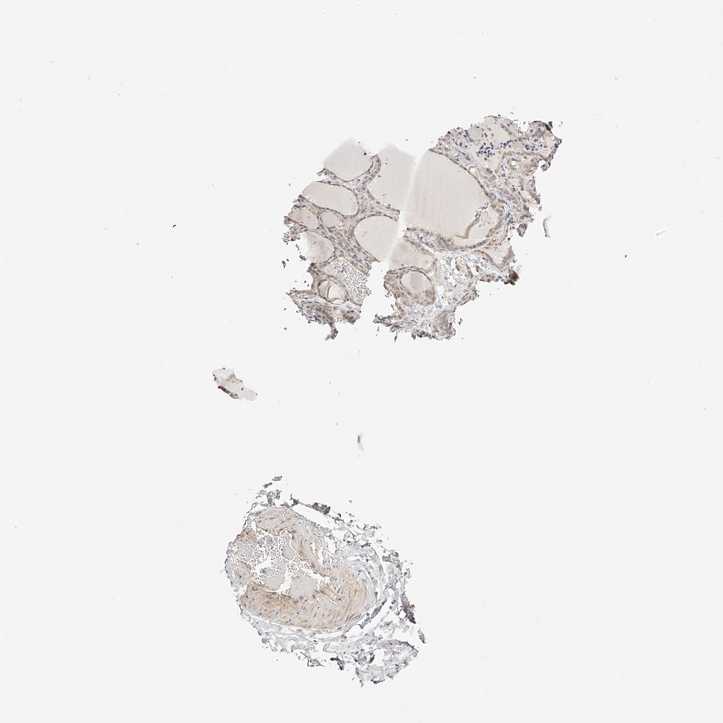

THYROID GLAND - Antibody stainingi

Antibody staining in the annotated cell types in the current human tissue is reported as not detected, low, medium, or high, based on conventional immunohistochemistry profiling in selected tissues. This score is based on the combination of the staining intensity and fraction of stained cells.

Each image is clickable and will lead to virtual microscopy that enables deeper exploration of all samples and also displays staining intensity scores, fraction scores and subcellular localization as well as patient and tissue information for each sample.

Antibody HPA028311Antibody HPA063549

Glandular cells LowLow